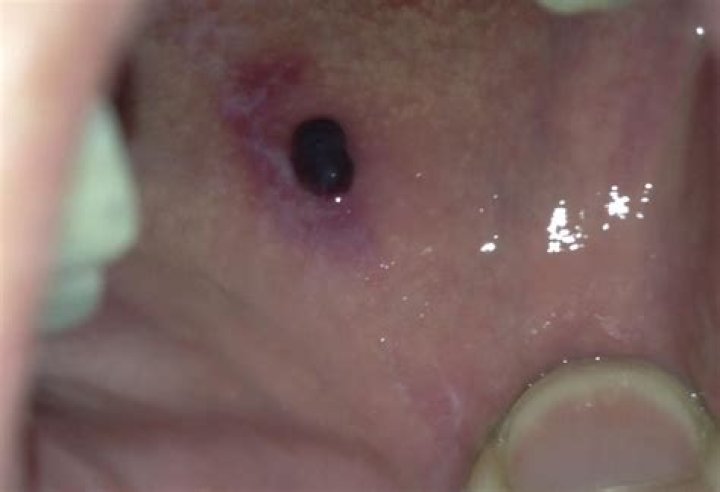

Tired of painful, unsightly blood blisters in your mouth? Discover the underlying causes and regain oral comfort.